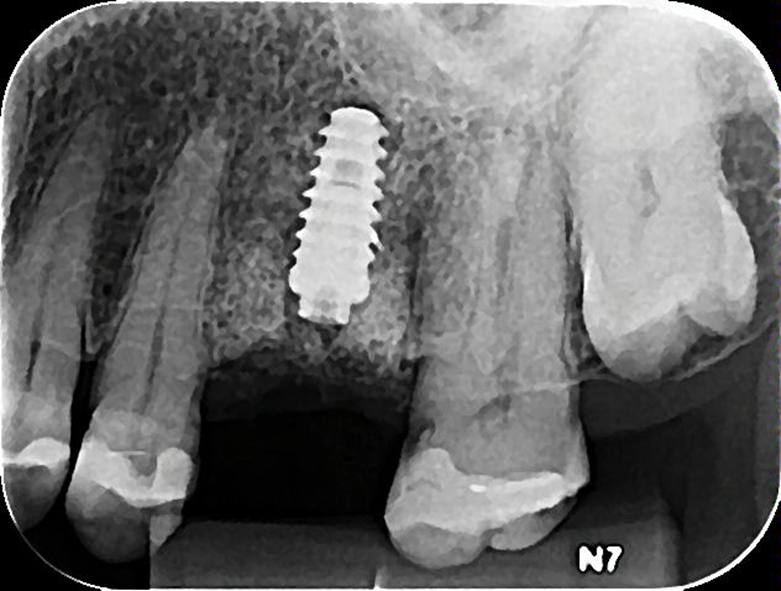

O Extra Graft é um biomaterial muito interessante para aplicação nestes casos, pois apresenta-se na forma de blocos fracionados (0,5g / 1g / 2g) e tem em sua composição 75% de hidroxiapatita (principal componente mineral do osso) e 25% de colágeno do tipo I (proteína mais abundante na porção orgânica do osso) – ambos de origem bovina. Devido a essa composição, possui grande atividade osteocondutora e maior adesão dos osteoblastos, aumentando a velocidade de neoformação óssea. Além disso, a porção de colágeno gera maior estabilidade do coágulo e ação hemostática, promovendo menor sangramento pós operatório e maior conforto ao paciente. O Extra Grafté de fácil manuseio e condensação dentro dos alvéolos e é radiopaco, facilitando a conferência do preenchimento via radiografia final do procedimento.

A sequência de imagens a seguir apresenta casos da aplicação clínica do Extra Graft em cirurgias de exodontia e implante imediato com preenchimento dos gaps, e apenas exodontia e preenchimento alveolar para favorecer a regeneração óssea.